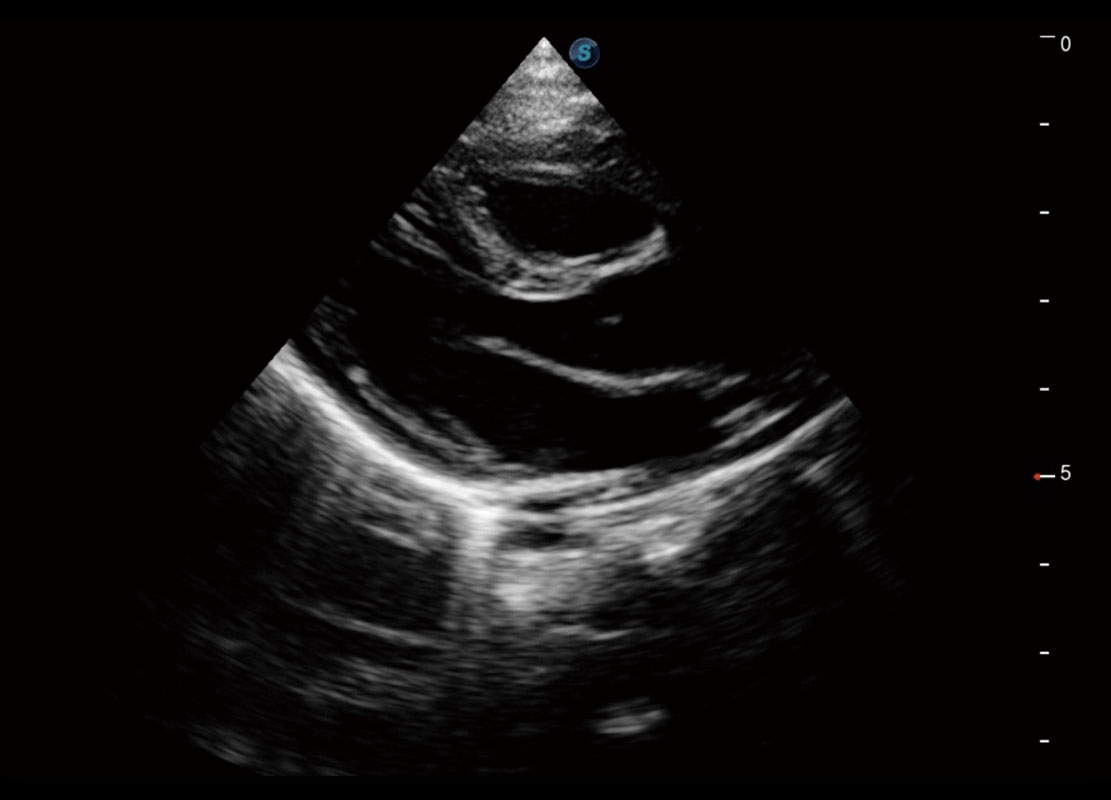

P60搭载一系列胎儿心脏成像技术,实现精细的胎儿心脏评估。

四腔切面

四腔心血流